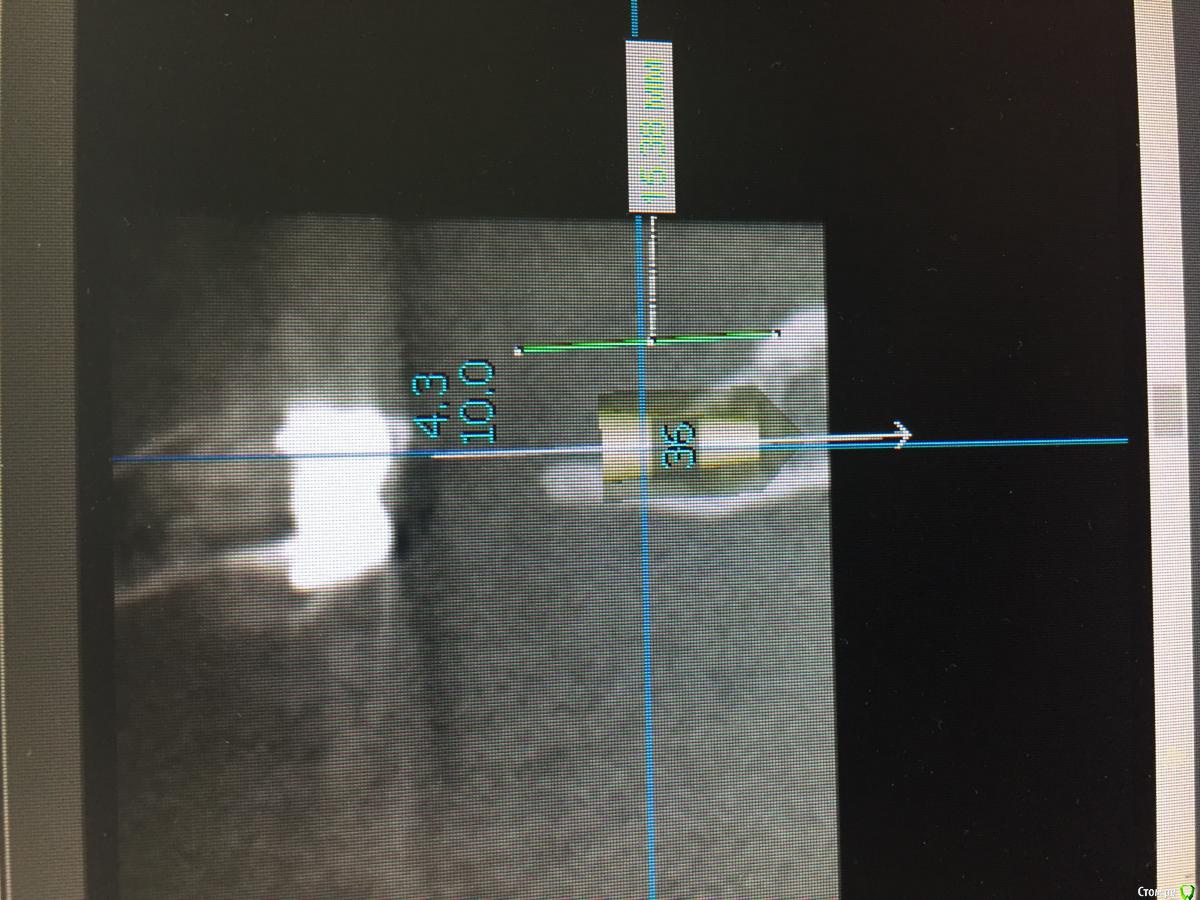

TIGER Опубликовано 27 ноября, 2016 Поделиться Опубликовано 27 ноября, 2016 не знаю почему фото перевёрнуто....но я бы поступил так 1 Ссылка на комментарий